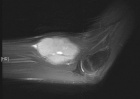

15 year old male seen c/o left elbow mass x5 years, significantly larger over 3 months

Zoom image: Radiological image Radiological image.